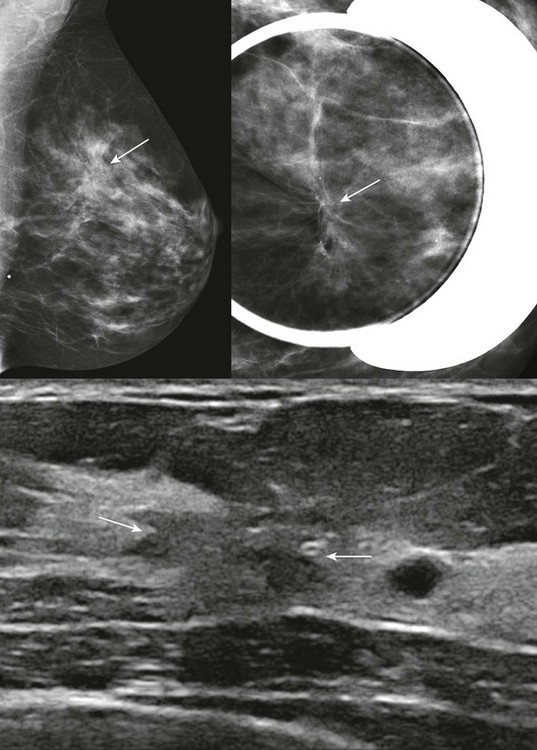

FIGURE 11-2 ILC.

A 49-year-old woman with a firm palpable lump in the right breast. Mammogram is normal in the palpable area that is marked by a triangle. US shows multiple hypoechoic areas with shadowing but no discrete mass, which is characteristic of ILC. (Reprinted with permission from Harvey JA. Unusual breast cancers: Useful clues to expanding the differential diagnosis. Radiology 2007;242:683-694.)

On US, ILC may present as a defined mass (see Fig. 11-3) but more often presents as ill-defined areas of shadowing without a distinct mass (see Fig. 11-2). The lines and arcs of tumor can produce bands of shadowing, like the edges of a spider web. Although tumor size is often underestimated by US, this modality is more accurate than clinical examination or mammography in assessing extent of disease.